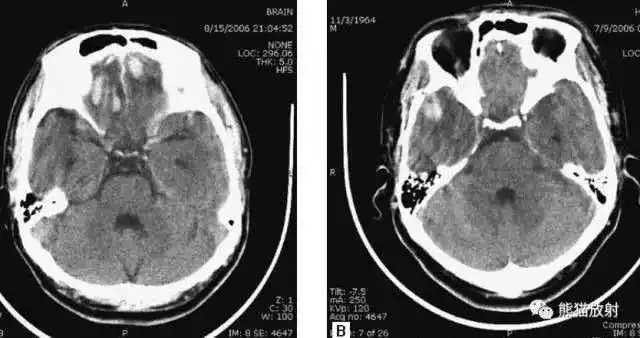

▲

动脉瘤破裂导致蛛网膜下腔出血、

脑室积血、非交通性脑积水。

与外伤性蛛网膜下腔出血不同,动脉瘤破裂导致的SAH常不累及大脑凸面,而位于基底池附近。脑动脉瘤常位于鞍上池的Willis环血管。

A:四脑室积血;

B:中脑导水管、环池、右侧侧脑室颞角积血,前交通动脉处(动脉瘤好发位置)出血密度较高;

C:三脑室积血;

D-F:侧脑室积血,蛛网膜下腔出血(血液代替了脑脊液)。